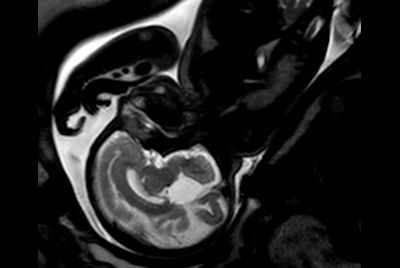

Fetal Arachnoid Cyst

Fetal Brain and Spine